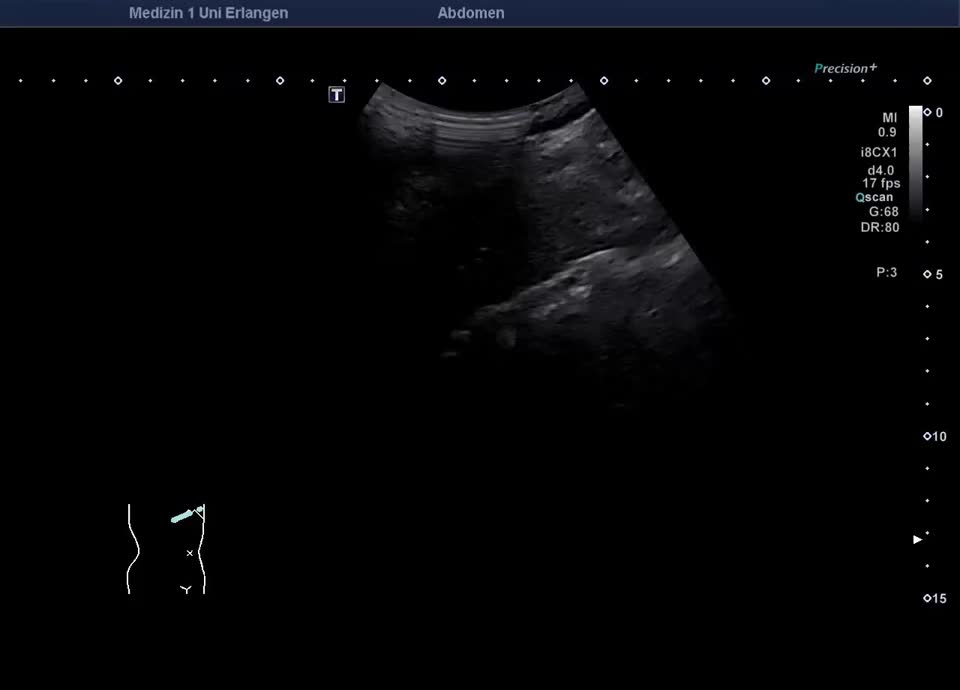

Kasuistik: 66-jähriger Patient mit seit der Jugend bekannter γ-GT-Erhöhung, sonographische Vorstellung zum Ausschluss eines cholangiozellulären Karzinoms. Sonographisch zeigt sich im B-Bild ein inhomogenes Leberparenchym mit diffus verteilten kleinen Kometenschweifartefakten im rechten Leberlappen. Das sonographische Bild ist vereinbar mit multiplen biliären Hamartomen (Von-Meyenburg Komplexe). Sie bestehen aus Zysten, die mit Gallengangsepithel ausgekleidet sind, und Bindegewebe, treten einzeln oder multipel auf und weisen typischerweise eine Größe von etwa 0,5–15 mm auf. Sonographisch stellen sie sich als echoreiche Noduli dar. Zum Ausschluss malignitätsverdächtiger Herdbefunde wurde eine kontrastmittelverstärkte Sonographie durchgeführt. Im CEUS zeigt das Leberparenchym in der portalvenösen und Spätphase homogenes Enhancement – die echoreichen Noduli sind isokontrastiert (Ausschluss Malignität). Die kleinen Zysten sind in allen Perfusionphasen nicht KM-aufnehmend. In Zusammenschau der Bildgebung und der bekannten γ-GT-Erhöhung besteht kein Anhalt für eine maligne Lebererkrankung. Eine einmalige sonographische Verlaufskontrolle wurde vereinbart.